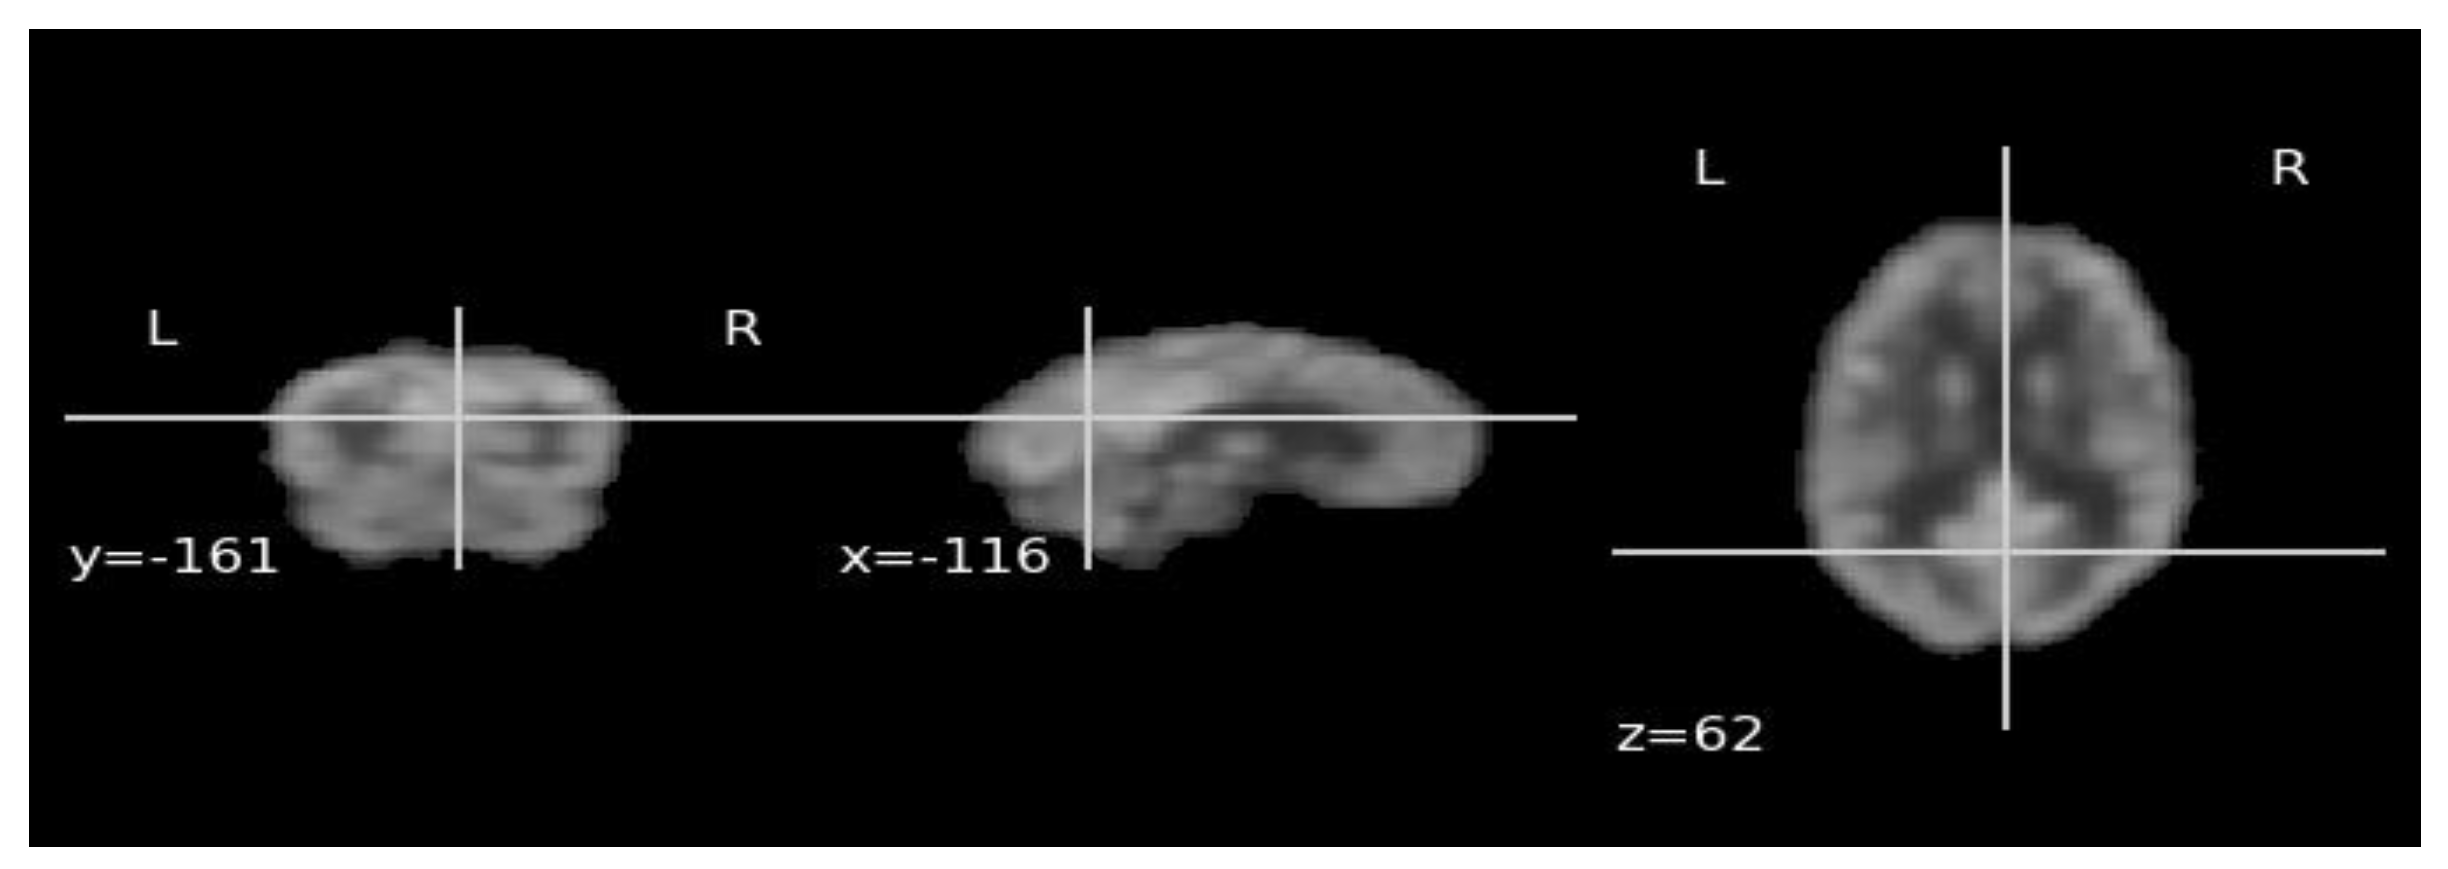

2.2. FDG-PET Image Acquisition and Preprocessing

2.5. 18F-FDG-PET Feature Learning with ViT-Dino